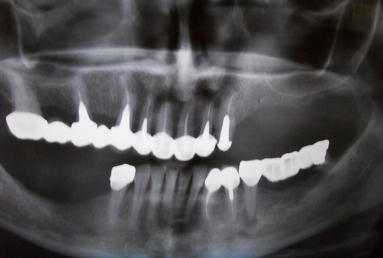

Initial situation: The patient needs dental implants on the left side of the maxillary jaw in order to have a fixed prosthetic restoration. But the bone is insufficient vertically and laterally, because the extractions were made a long time ago, which caused the extreme bone resorption and the vertical migration of the sinus floor.